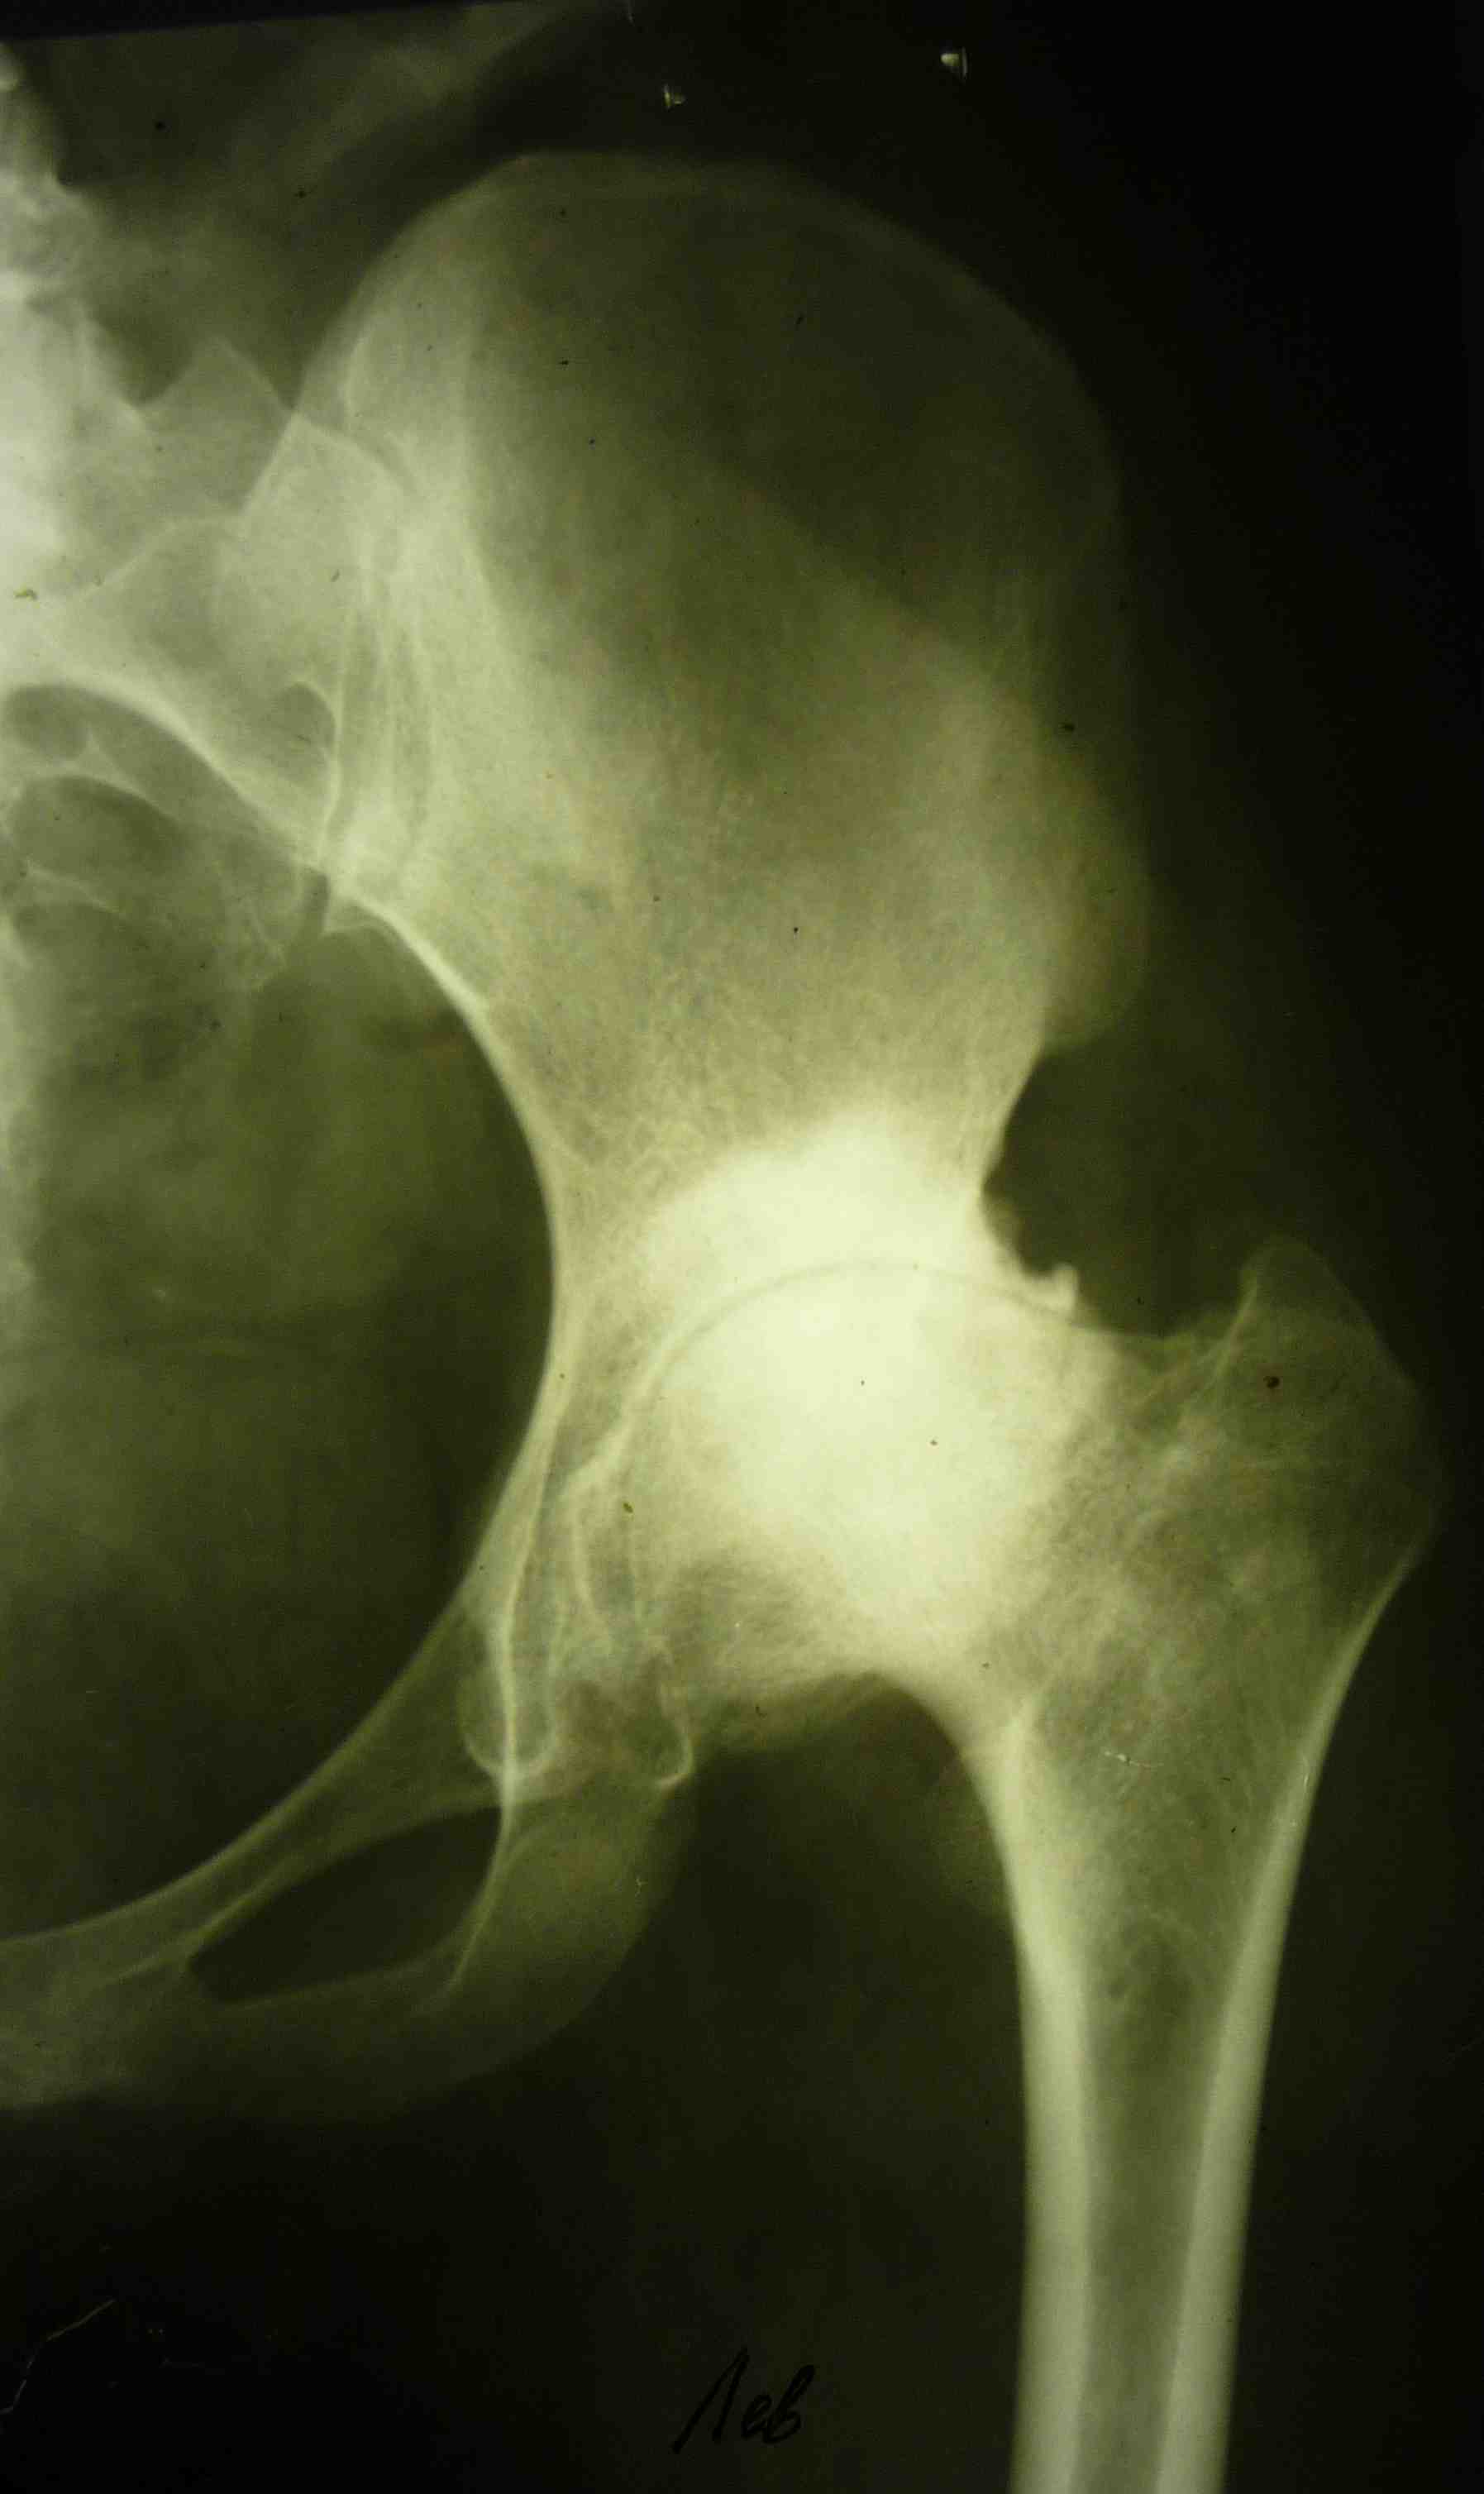

[Ortho] эндопротезирование коленного сустава

В настоящее время нет возможности сделать осевые снимки всей конечности.

Это всё чем я раполагаю на сегодняшний день.